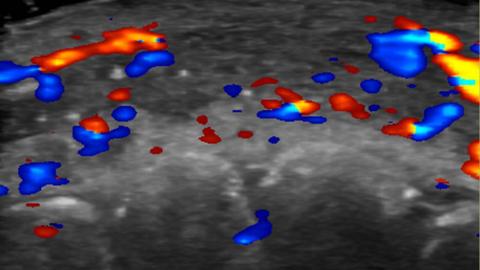

Researchers used ultrasound to study 100 cases of filler injections that had gone wrong.

Clinics are now being advised to carry out ultrasounds before giving dermal fillers in the face, to avoid harming any nearby arteries.